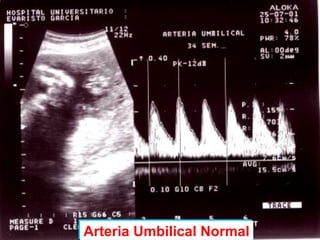

- Detecta presencia y

dirección del flujo en un

vaso

- Diferencia flujo laminar o

turbulento

- Valora grado de resistencia

que el flujo tiene que vencer

para alcanzar un órgano

Arteria Umbilical NormalArteria Umbilical Normal